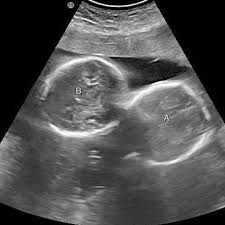

इंदौर। इंदौर के ESIC अस्पताल से प्रेगनेंसी का एक बेहद चौंकाने वाला मामला सामने आया है. यहां पर एक महिला ने तीन बच्चों को जन्म दिया. इससे भी ज्यादा हैरान कर देने वाली ये है कि जब डॉक्टर ने डिलीवरी से पहले अल्ट्रासाउंड किया था तब रिपोर्ट में दो बच्चे ही दिख रहे थे. लेकिन जब महिला ने तीन बच्चों को जन्म दिया तो डॉक्टर भी हैरान रह गए।

हॉस्पिटल के डॉक्टरों का मानना है कि ऐसे केस मेडिकल फील्ड के रेयर केसेस में से एक होते हैं. महिला ने 1 बेटा और 2 बेटियों को जन्म दिया है. अधिकारी ने बताया कि कर्मचारी राज्य बीमा निगम (ईएसआईसी) के चिकित्सा महाविद्यालय से जुड़े अस्पताल में 27 वर्षीय महिला ने दो लड़कियों और एक लड़के को रविवार (29 मार्च) को सामान्य तरीके से जन्म दिया. इस प्रसव के बाद जच्चा व तीनों नवजात शिशु स्वस्थ हैं।

महाविद्यालय की सहायक प्रोफेसर डॉ. रुचि जोशी ने ‘पीटीआई-भाषा’ को बताया, कि प्रसव के तय समय से पहले पैदा हुए तीनों बच्चों का वजन 1.70 किलोग्राम से 1.90 किलोग्राम के बीच हैं, इनता ही नहीं जन्म के तुरंत बाद से इन बच्चों को विशेष देखभाल प्रदान की जा रही है. उन्होंने आगे बताया कि इंदौर के पास स्थित पीथमपुर औद्योगिक क्षेत्र की रहने वाली महिला दूसरी बार मां बनी है और उसकी एक बेटी पहले से है।

डॉक्टरों का कहना है कि डिलीवरी जोखिम भरा जरूर था लेकिन डॉक्टर की सतरकता ने प्रसव आसानी से हो पाया. डॉक्टर ने आगे बताया कि तीन बच्चों की डिलीवरी थोड़ी कॉम्पलेक्स होती है. साथ ही यहां तो रिपोर्ट और रियलिटी में भी अंतर देखने को मिला है. डॉक्टर ने हिम्मत रखते हुए स्थिति को कंट्रोल किया और मॉनीटर किया. अभी जच्चा बच्चा चारों स्वस्थ हैं।